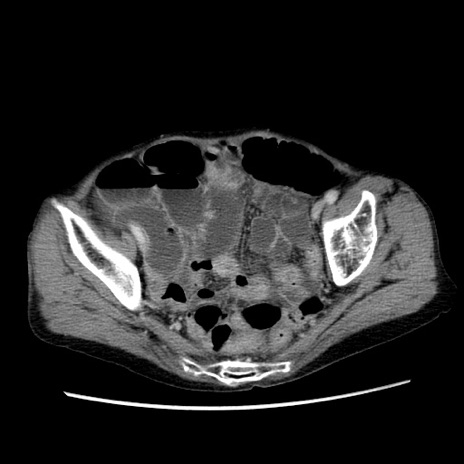

冠状断像